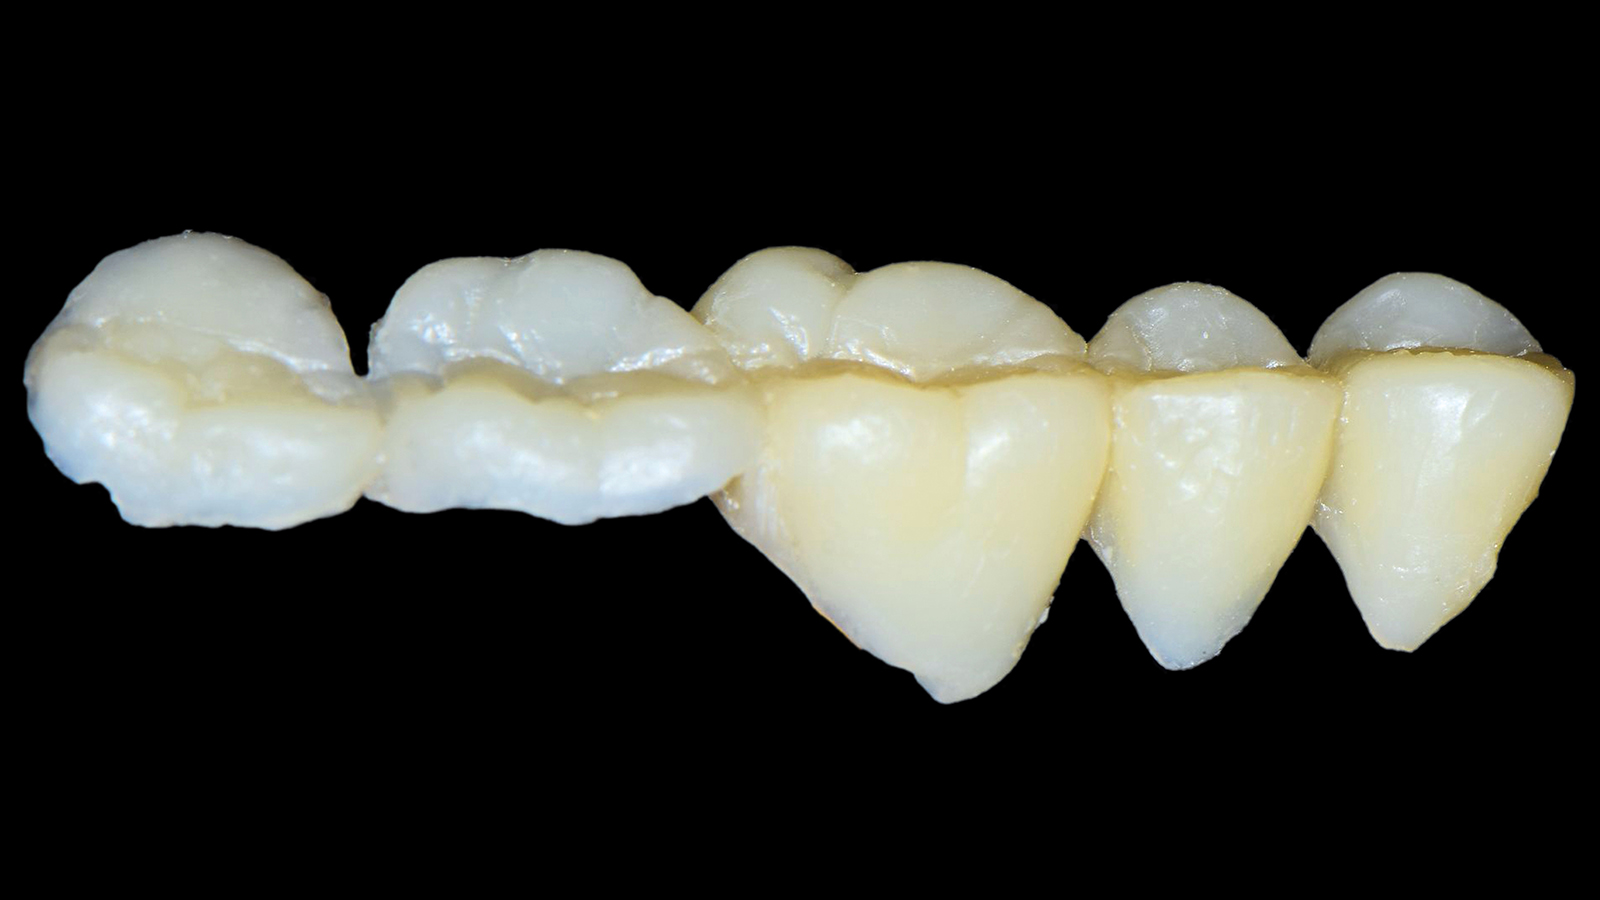

A high-viscous composite such as Charisma Diamond or Charisma Topaz can be used as capping layer if preferred. This allows the creation of the natural morphology in the occlusion which is requested e.g. in case of big cavities or cusp replacement. Any shade can basically be used based on individual preferences. Especially the Charisma Diamond/ Charisma Topaz ONE Shade promises the same colour adaptation to the surrounding dentition like Charisma Bulk Flow ONE.

Charisma Bulk Flow ONE is a flowable bulk-filling composite with curing depths of up to 4mm whereas the high-viscous composites Charisma Classic as well as Charisma Diamond and Charisma Topaz in ONE Shade are applied in incremental layering techniques in 2mm. The different viscosities and application techniques imply different benefits complementing eachother in everyday posterior restorations.